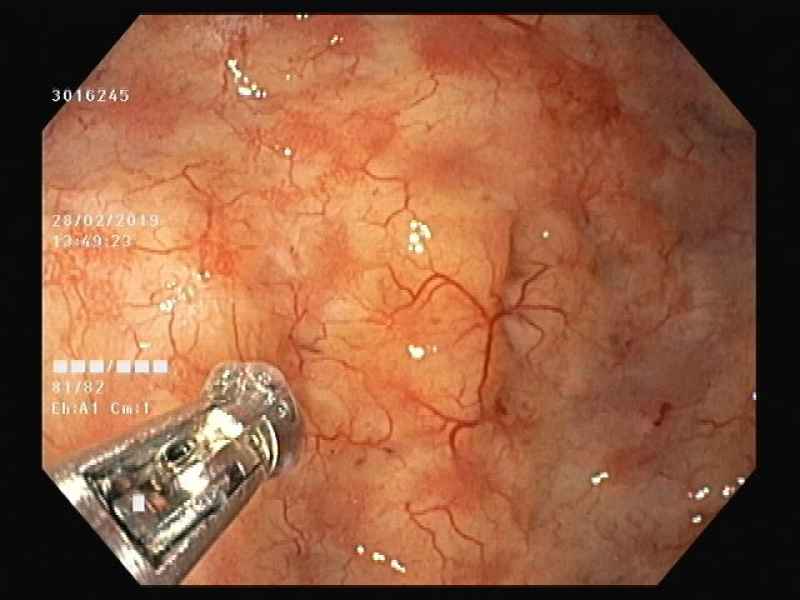

A mantle of rosaries along the colon - 2.º Prémio (Fotografia)

Fotografias